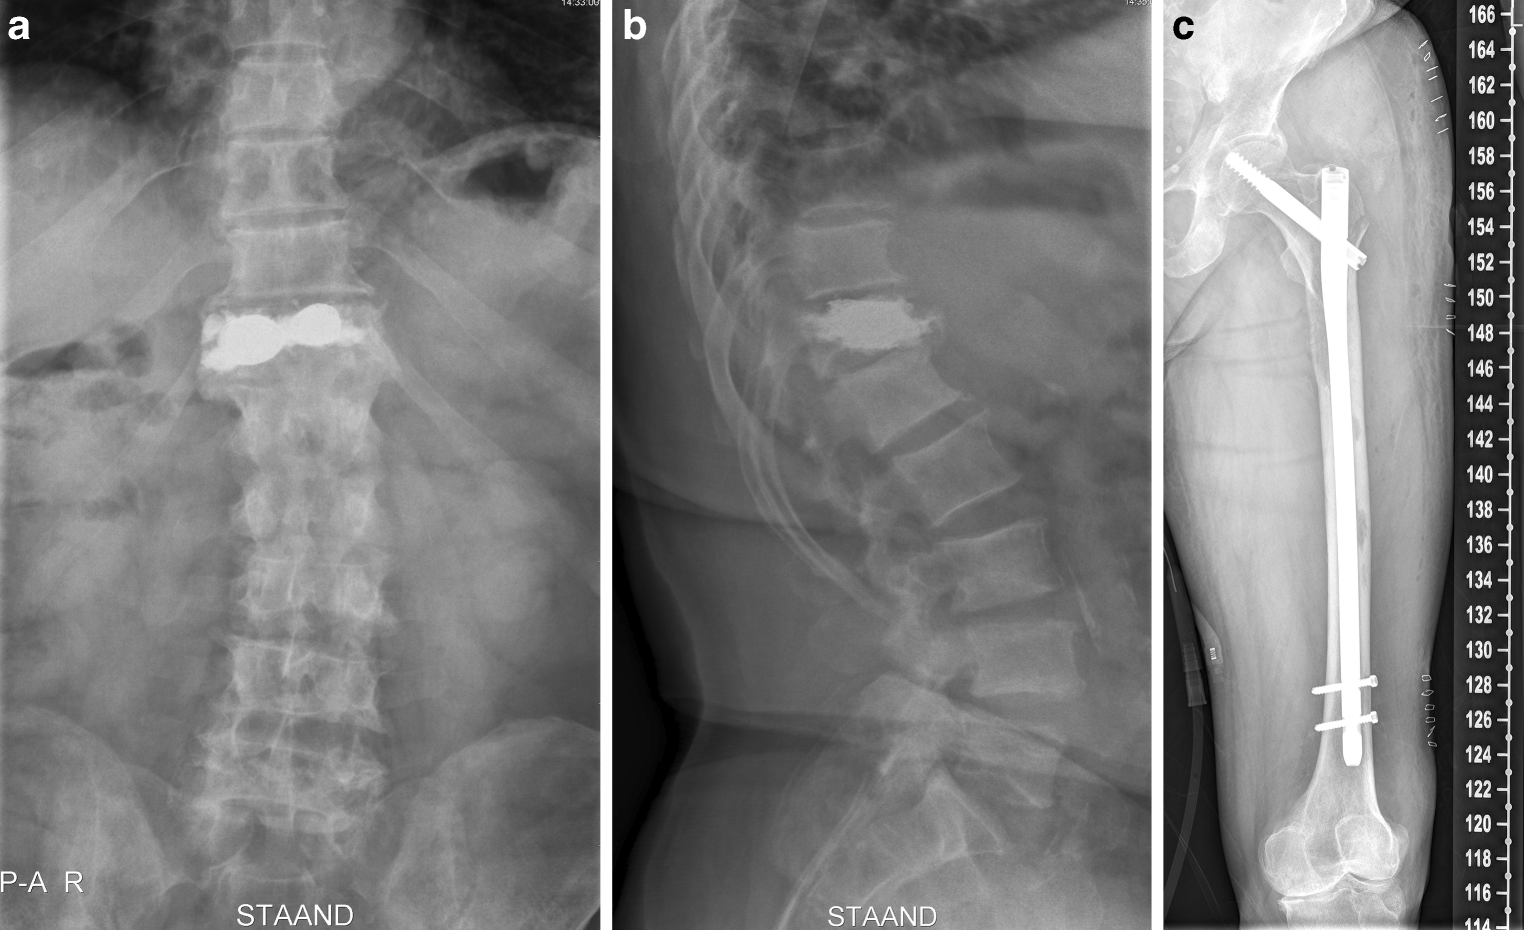

Patiënt A, een 68-jarige, uiterst actieve man die nog dagelijks fysieke zwaar werk verricht, wordt in oktober 2018 door de huisarts, primair voor de neuroloog, ingestuurd in verband met sinds drie weken bestaande progressieve loopstoornissen, verminderde kracht in beide benen, en tintelingen in beide armen en benen. De voorgeschiedenis vermeldt hypertensie en de verdere anamnese levert geen bijzonderheden op. Bij lichamelijk onderzoek wordt een vitale man gezien. Aan hart, longen en abdomen geen afwijkingen. Bij rectaal toucher een vast aanvoelende prostaat verdacht voor een T3-prostaatcarcinoom. Neurologisch onderzoek: moeizaam, spastisch looppatroon, verhoogde reflexen en bilaterale Babinski’s. Aanvullend onderzoek is verricht. Laboratoriumonderzoek: Hb 9,0 mmol/l, eGFR 84 kl/1,73m2, AF 119 IU/l en PSA 2165 ng/ml, verder geen afwijkingen. Skeletscintigrafie: uitgebreide ossale metastasen. CT thorax/abdomen: uitgebreide regionale en extraregionale pathologische lymfeklieren verdacht voor metastasen. MRI wervelkolom: meerdere metastasen in cervicale, thoracale en lumbale wervelkolom, met ter hoogte van C5 evidente compressie op het myelum. Concluderend, een patiënt met een incomplete dwarslaesie C5 door lokale tumorprogressie op basis van de klinisch diagnose cT3N1M1a/b-prostaatcarcinoom. Patiënt is direct behandeld met dexamethason i.v. en vervolgens oraal. Daarnaast is gestart met hormonale therapie, direct een antiandrogeen en een week later een LHRH analoog. De volgende dag is hij door de orthopedisch chirurg geopereerd, waarbij een spondylodese posterieur C3-Th1 (fig. 1) met decompressie C4–C7 is uitgevoerd, met uitgebreide excisie van tumorweefsel. De PA van het verwijderde weefsel laat een metastase-adenocarcinoom van de prostaat zien, Gleason 8 (4 + 4) met cribriforme groei. Het direct postoperatief herstel was goed. Zeven dagen later ontwikkelt hij echter een incompleet caudasyndroom met onvermogen tot mictie en defecatie. De volgende dag wordt hij wederom geopereerd, waarbij een decompressie L3–L5 wordt uitgevoerd. Hierna wordt hij in goede conditie ontslagen. Ruim drie weken later is hij bestraald (1 × 8 Gy) op C3-Th4 en L2-S2. Omdat hij nog niet fit genoeg is voor chemotherapie, wordt hij aansluitend behandeld met abiraterone/prednison met daarnaast calcichew en ibandroninezuur. Bij de laatste controle in juli 2019 vergaat het hem uitstekend. Hij is volledig hersteld, klachtenvrij en heeft zijn werkzaamheden hervat. Het PSA is 0,57 ng/ml.

Figuur 1

Patiënt A: anterieure (a) en laterale (b) röntgenfoto van de spondylodese posterieur C3-Th1 met decompressie C4–C7